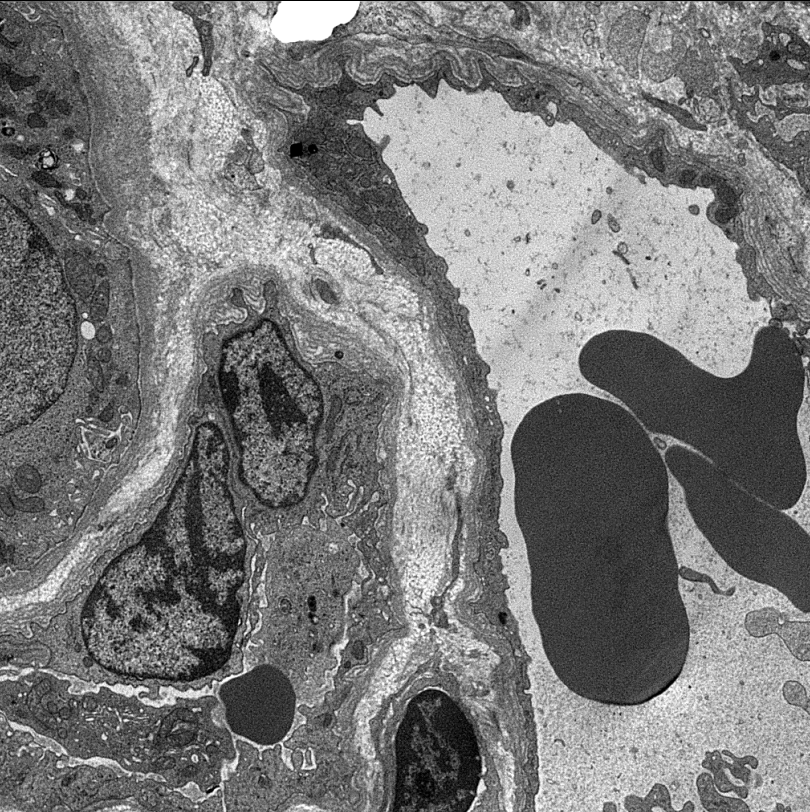

I capillari peritubulari originano dalle arteriole efferenti del glomerulo renale, circondano l'interstizio tra i tubuli renali ed assorbono osmoticamente le sostanze dalla preurina contenuta nei tubuli stessi, come sodio, glucosio, ione bicarbonato (HCO3-) e acqua.

Dal capillare peritubulare origina una venula (venula renale) che raggruppandosi, entra nella composizione della vena renale la quale uscendo dall'ilo del rene affluisce nella vena cava inferiore.